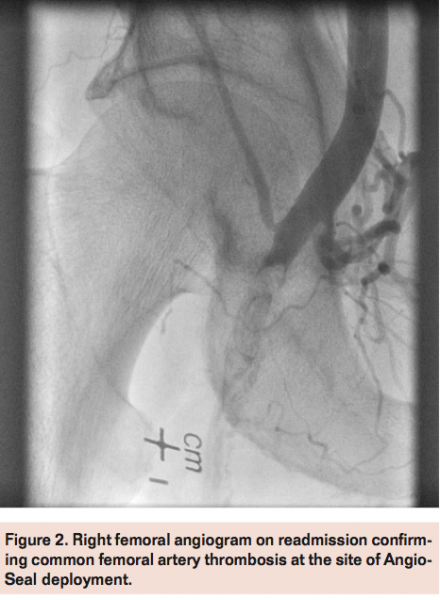

Access was obtained in the left femoral artery with a 7 Fr sheath. Angiography of the right external iliac artery with runoff demonstrated a hazy thrombotic 20 mm subtotal occlusion of the right common femoral artery at the site of previous Angio-Seal device deployment with filling of the distal common femoral artery via microchannels (Figure 2). A Grand Slam wire (Abbott Vascular) was advanced across the lesion into the distal popliteal artery and a Spider 6.0 mm distal embolic protection device (Covidien) was deployed in the popliteal artery. Directional atherectomy with a TurboHawk LSM device (Covidien) was performed (Figure 3) with multiple cuts to eliminate the residual Angio-Seal anchor and collecting some atheroma (Figure 4). The filter was retrieved successfully, which also revealed a moderate amount of macro debris (Figure 4). Final angiogram after adjunctive balloon angioplasty demonstrated good angiographic result with brisk flow through the common femoral artery and minimal residual luminal irregularities (Figure 5).

The patient was discharged home the following day without any complications. At follow-up in clinic 1 month later, there were no recurrent symptoms and palpable pedal pulses.